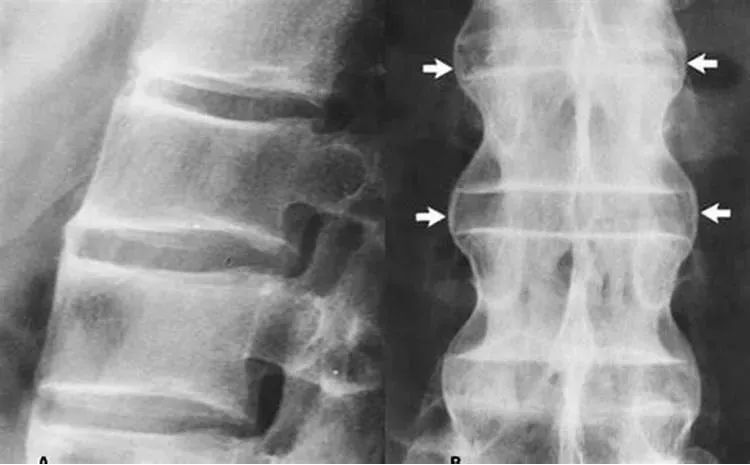

強(qiáng)直性脊柱炎的診斷主要基于患者的癥狀、體格檢查和影像學(xué)檢查,醫(yī)生可能會(huì)詢問患者的家族史和個(gè)人史,以了解可能的病因,血液檢查、X光、MRI等影像學(xué)檢查有助于確診強(qiáng)直性脊柱炎。